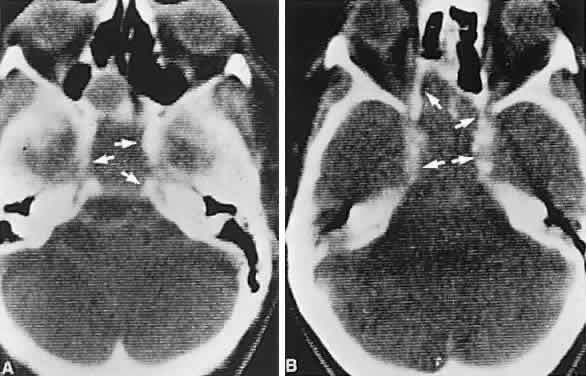

Fig. 4. Magnetic resonance imaging of a suprasellar meningioma (TR, 600 milliseconds; TE, 20 milliseconds). A. Coronal section of a large meningioma (large arrows), isodense to brain. B. Sagittal section. Note the normal sella and pituitary gland (p). Sagittal (C) and coronal (D) sections of a planum meningioma, extending into the sella. Note the upward deflection of the chiasm (arrow in C) and extension to the cavernous sinus (arrows in D).

In previous decades, chiasmal interference with optic atrophy, but “normal” plain skull films, was referred to as “Cushing's syndrome of the chiasm,” caused by meningiomas, aneurysms, or other noncalcified suprasellar lesions. The modern neuroimaging techniques of enhanced CT, “bone-window” protocols, and gadolinium-contrasted MRI are now exceedingly sensitive in disclosing meningiomas or other parachiasmal masses (Fig. 4). At present, contrast-enhanced CT or MRI precisely demonstrate extra-axial tumor configuration; CT is superior in disclosing calcification or bone changes, but it is inferior for assessing suprasellar or intrasellar extension, postsurgical changes, and vascular displacement or encasement.76 Whether MRI or even MR angiography obviates standard selective arteriography, especially when surgical intervention is contemplated, is moot.